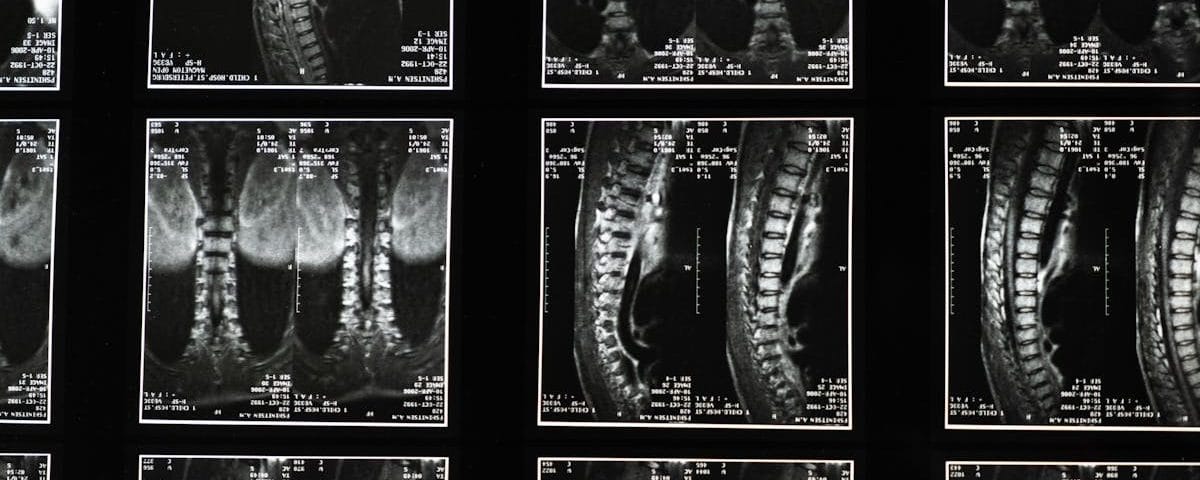

La sciatalgie, souvent associée à des douleurs irradiantes dans le bas du dos et les jambes, est une condition fréquente qui peut affecter la qualité de vie. Elle résulte d’une compression ou d’une irritation du nerf sciatique, qui s’étend du bas du dos à l’arrière des jambes. Divers facteurs peuvent contribuer à la sciatalgie, notamment les hernies discales, les tensions musculaires ou des changements dégénératifs dans la colonne vertébrale. Pour soulager cette douleur, des exercices spécifiques sont souvent recommandés, visant à étirer et à renforcer les muscles du dos et des jambes.